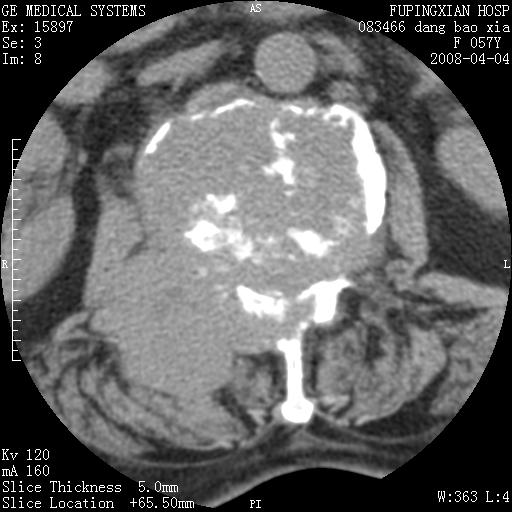

标题: CT12677:女性,57岁,疼痛数月。 [打印本页]

标题: CT12677:女性,57岁,疼痛数月。

椎体及附件骨质破坏同时伴软组织肿块,首先考虑恶性肿瘤。

骨组织起源,膨胀,软组织肿块=恶性改变:首选骨巨,其次转移瘤,再次脊索瘤

椎体及附件骨质破坏,伴软组织肿块,首先考虑恶性,不排除转移瘤.

椎体及附件溶骨性破坏,周围巨大软组织肿块,首先考虑转移瘤。